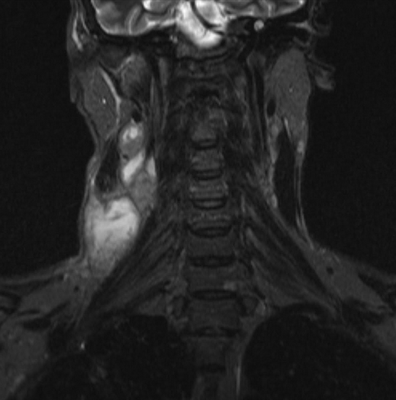

Туберкулезный лимфаденит на снимке МРТ

МРТ мягких тканей шеи